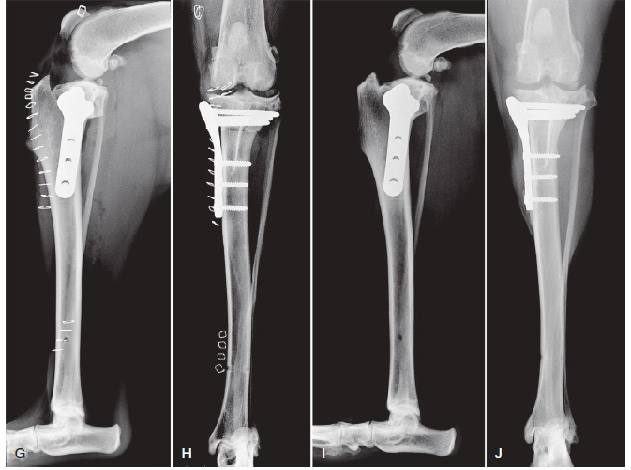

TPLO(tibial plateau leveling osteotomy) поворачивает плато большеберцовой кости таким образом, что меняет биомеханику сустава так, что, что при сгибании сустава бедренная кость больше не сдвигается назад, достигается снятие нагрузки с наклона плато большеберцовой кости, и, как следствие, необходимость в передней крестообразной связке отпадает.

TTO(triple tibial osteotomy) – биомеханические основы работы этого метода схожи с методом TPLO, только при выполнении этого метода уменьшение угла скоса большеберцового плато достигается не за счет поворота плато, а за счет выпиливания клина в большеберцовой кости.